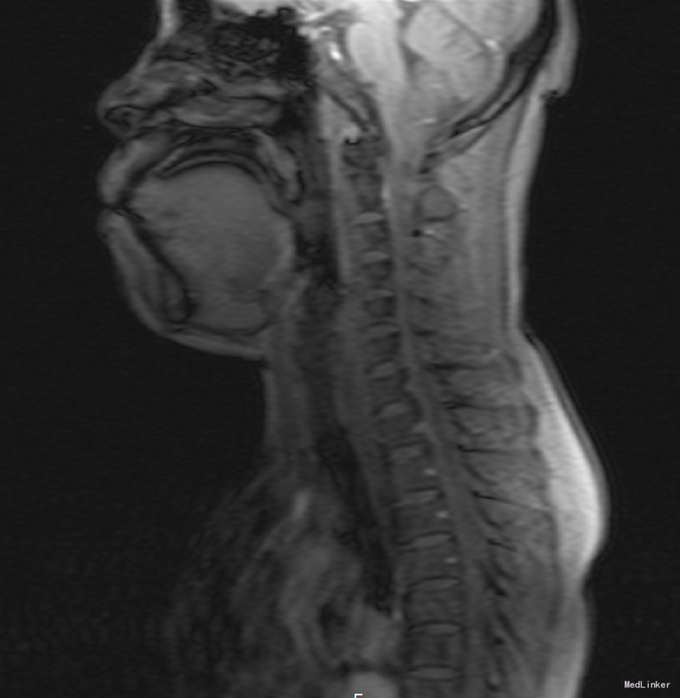

患者,女,50岁,因“左上肢麻木2年余,后颈部疼痛半年余”入院。

四肢自主活动,肌力V级,双上肢浅感觉减退,深感觉正常,病理征阴性。 本院颈椎MRI示“延髓及约颈1-6椎体水平颈髓髓内肿瘤,室管膜瘤可能性大,胶质瘤(毛星)待排。”

初步诊断:脊髓肿瘤。全麻下行[C2-6]脊髓髓内肿瘤切除术,术后给予头孢呋辛针 1.5g ivgtt q8h预防感染及止血、营养神经、补液、对症等治疗。

术后常规病理示:脊髓髓内室管膜瘤。